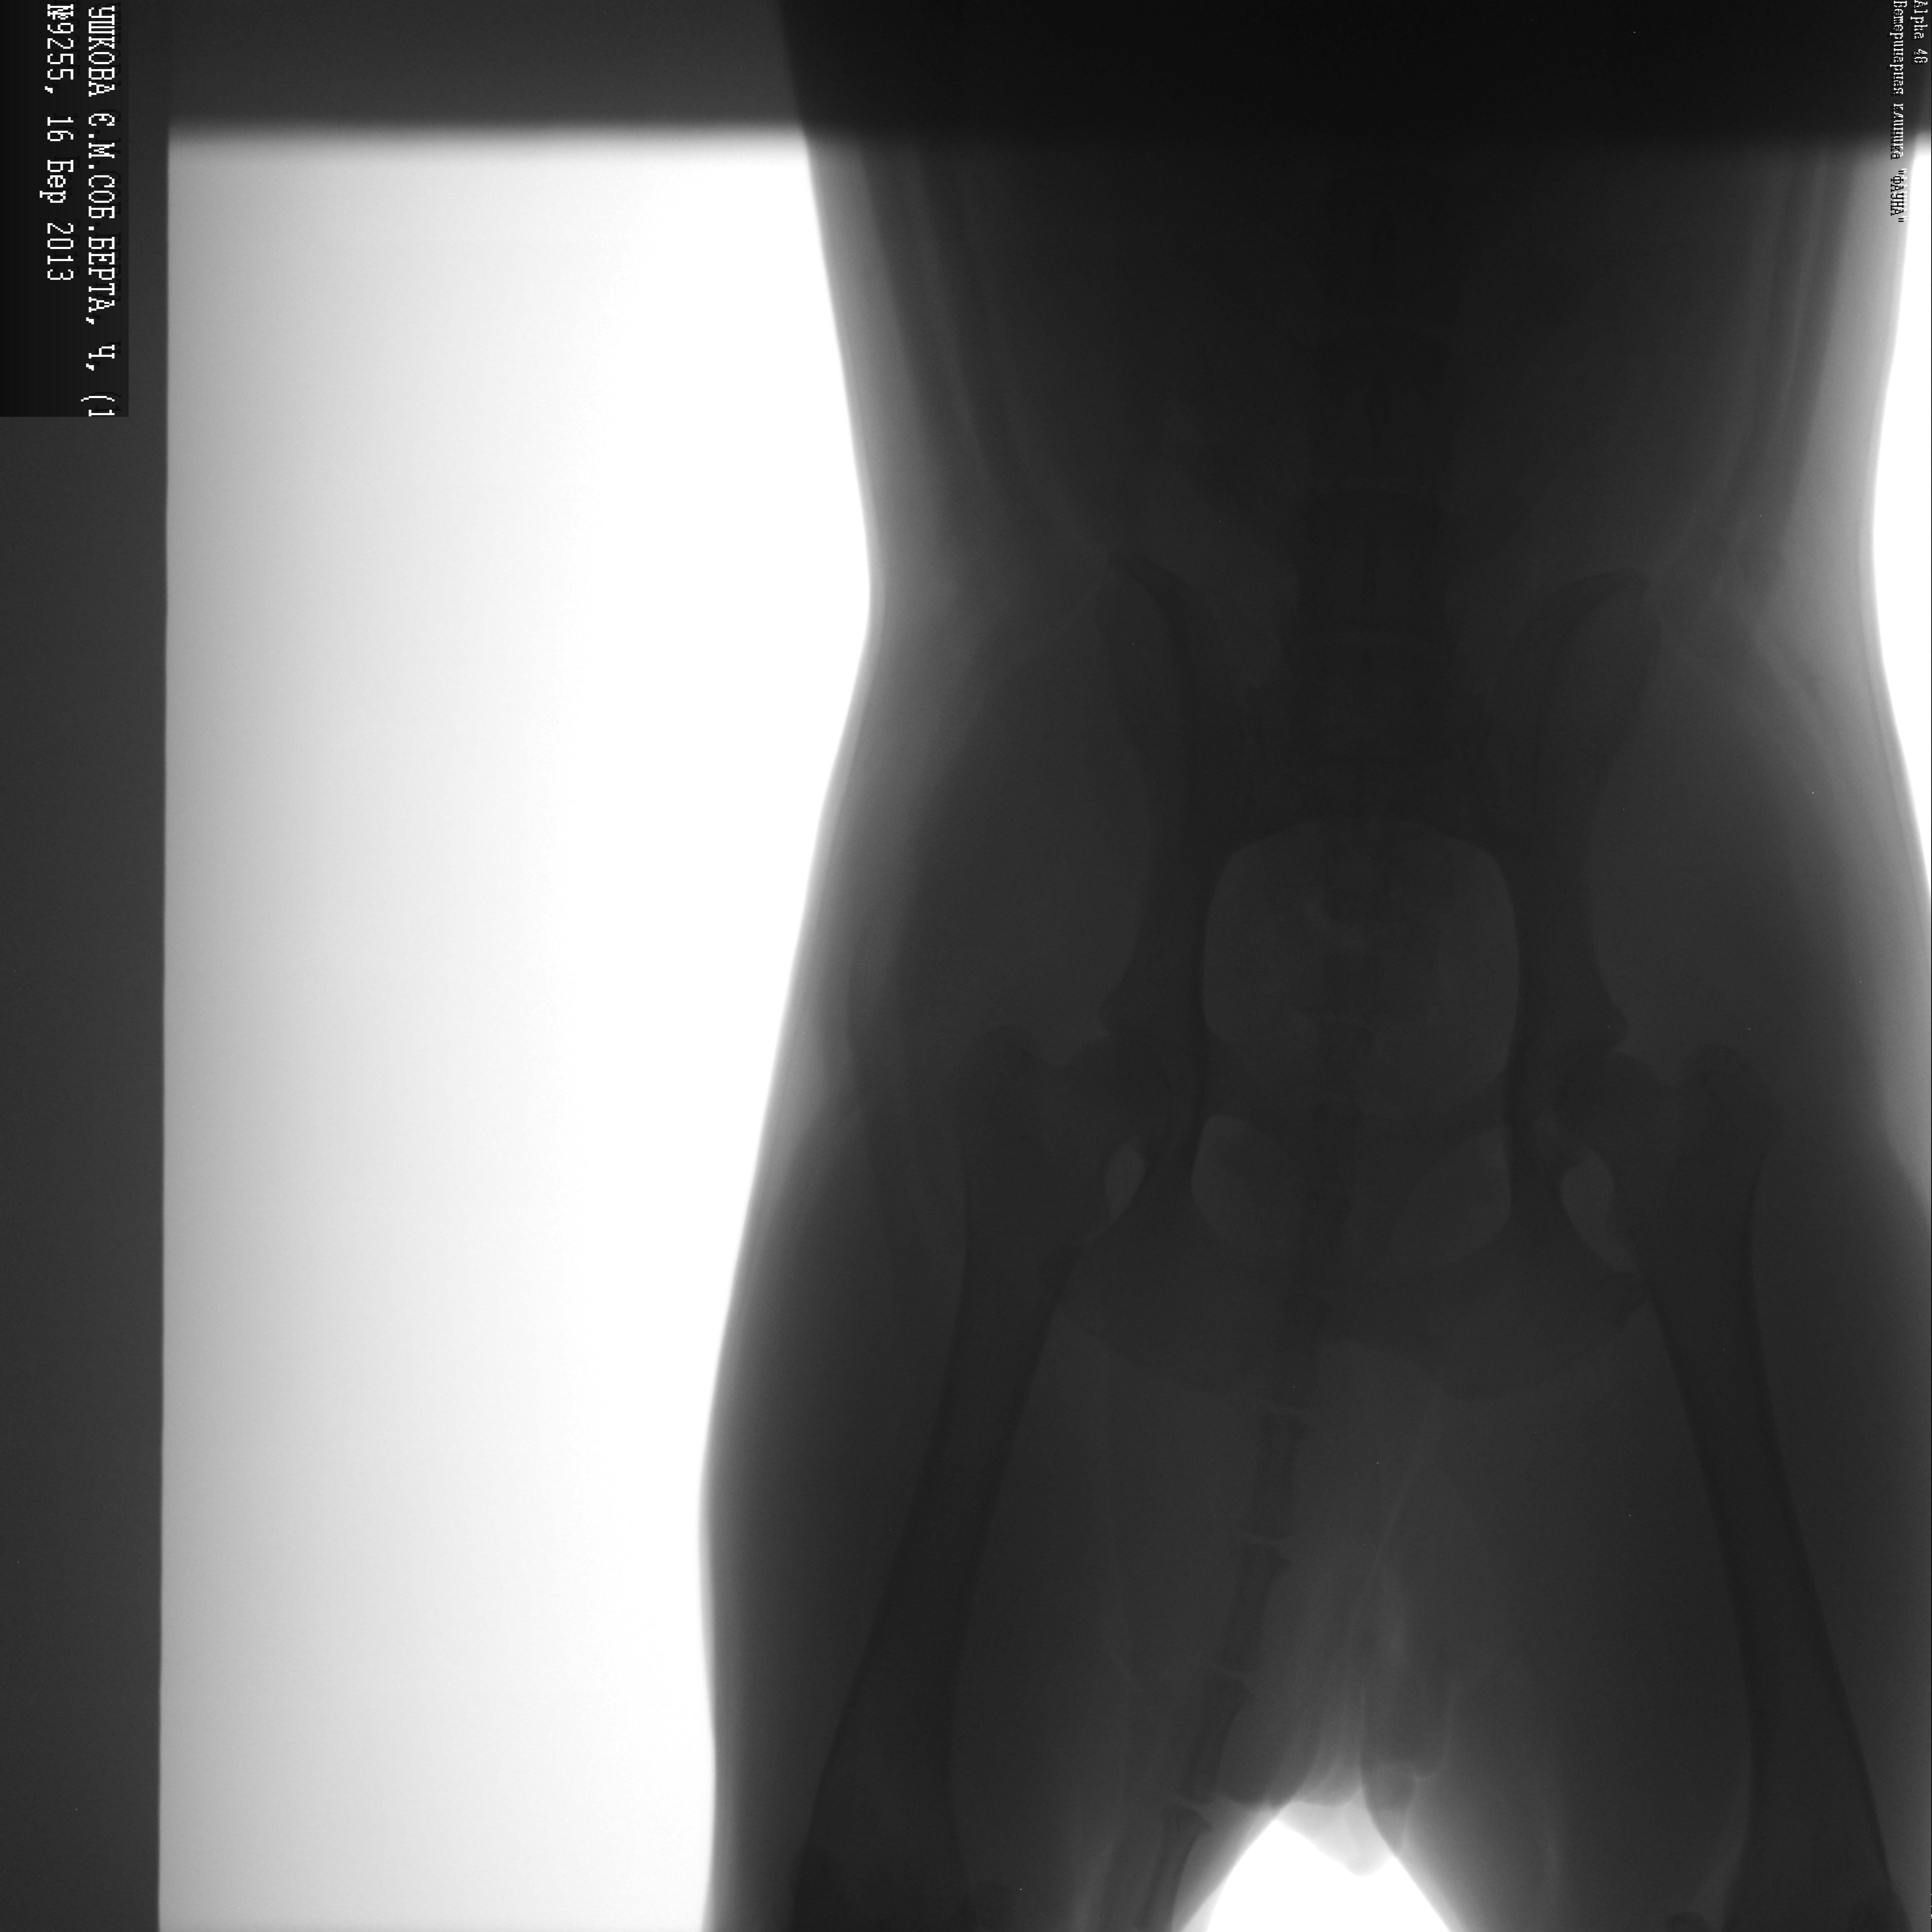

Здравствуйте!назначила местная сельская наша ветеринар лечение- тиотриазолин 2мл раз в день 10 дней,линкомицин 2 мл 1 раз в день-10 дней подряд,и мовалис 3 зня по 1 мл 1раз в день,поставила диагноз ревматизм. |